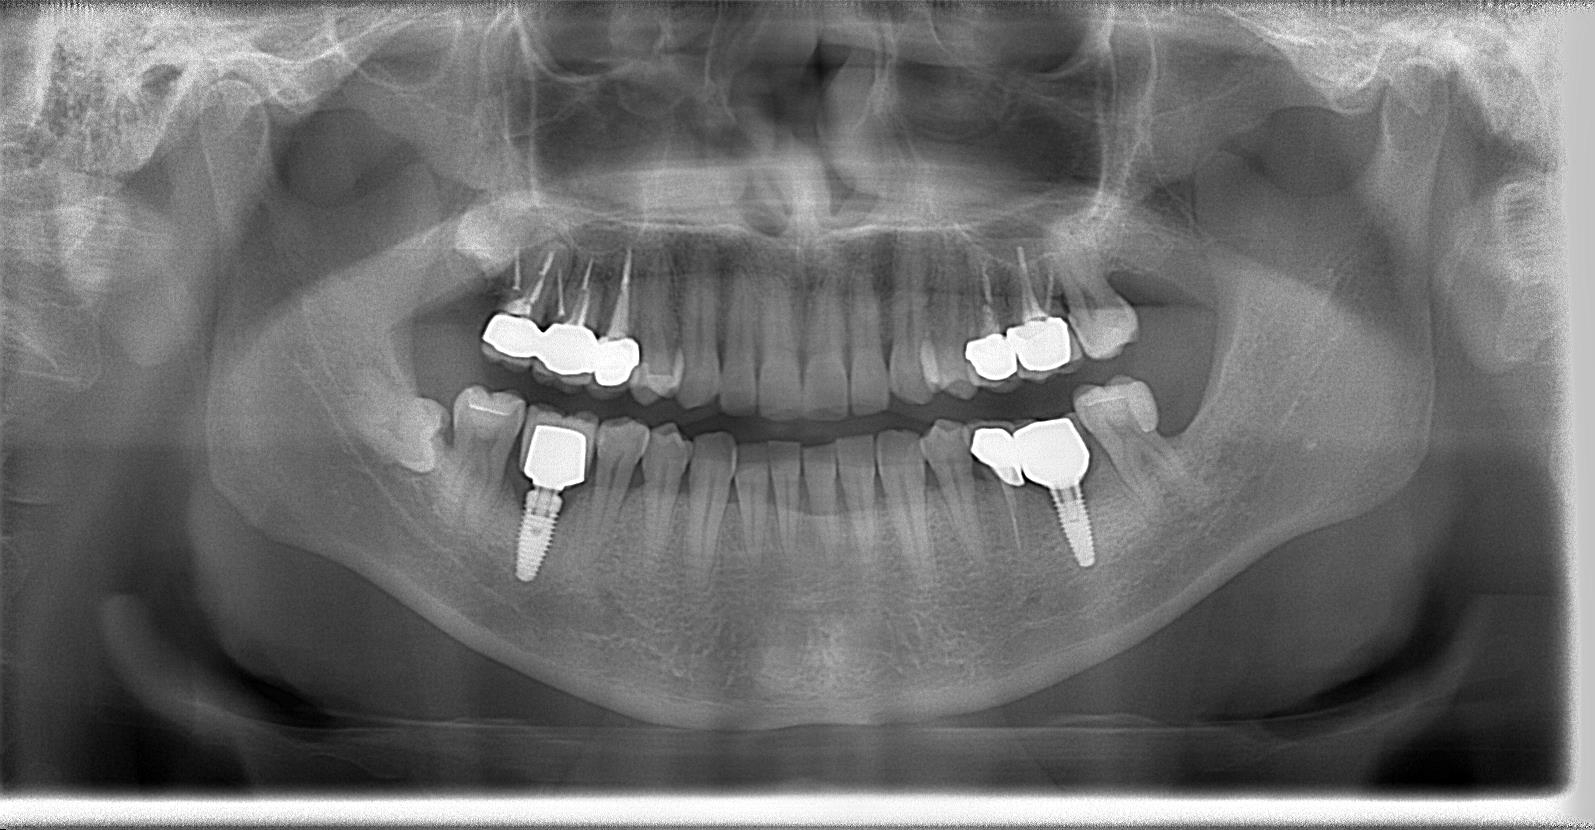

術前パノラマレントゲン写真

インプラント体1次埋入の術後パノラマレントゲン写真

術後パノラマレントゲン写真